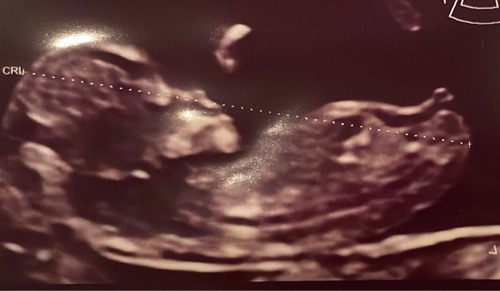

Echo met 12 weken, wat denken jullie? Met 11 weken dacht ik duidelijk een nub te zien wat dan een meisje zou zijn, maar deze zie ik het niet 🙈

Wat denken jullie?

Wat denken jullie. Een meisje of een jongetje in juli? Echo is 13+2 dagen � ...